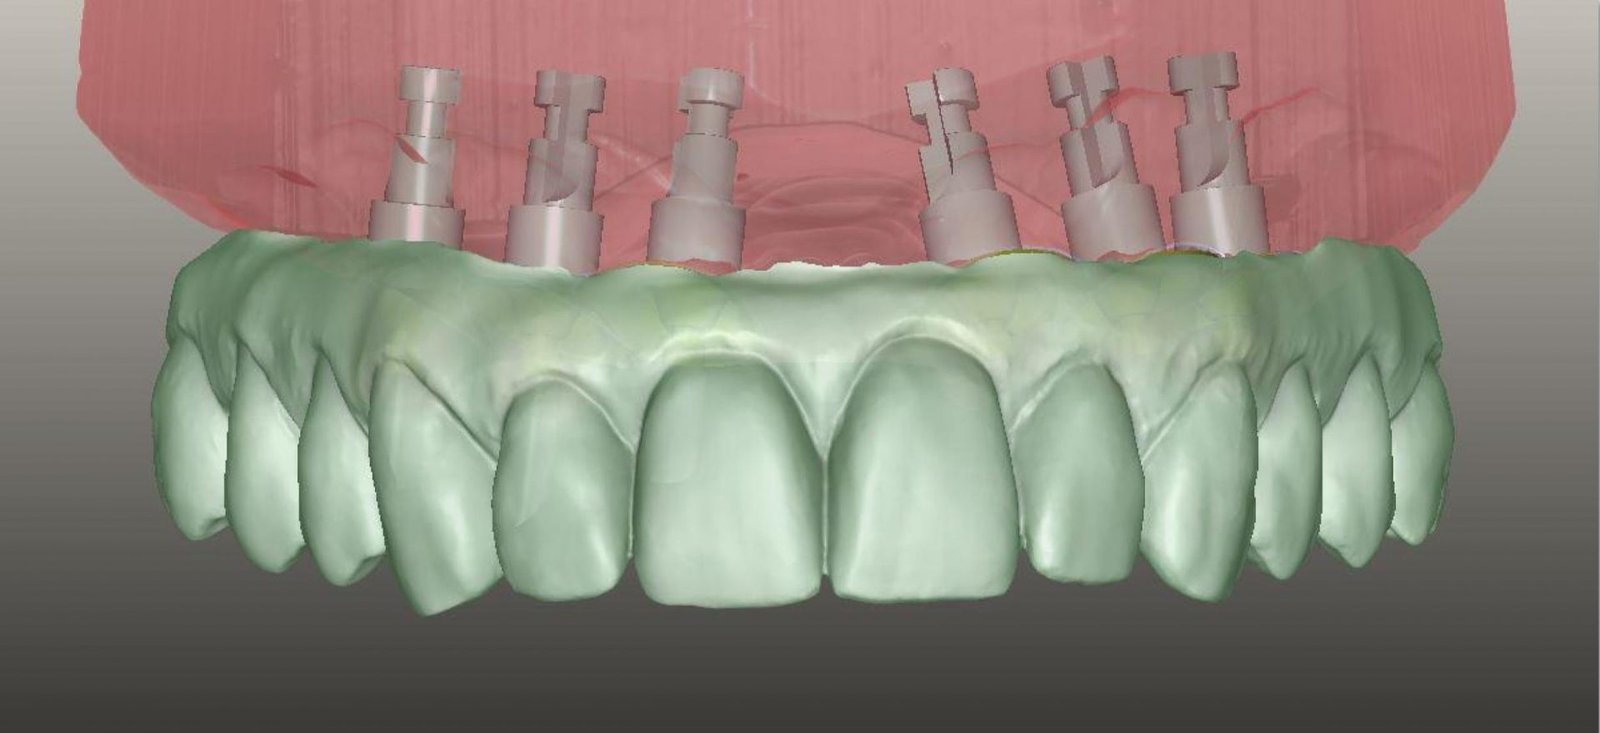

Ψηφιακή αποτύπωση και ολοκλήρωση των νέων δοντιών

Zirkonzahn-CAD/CAM workflow.